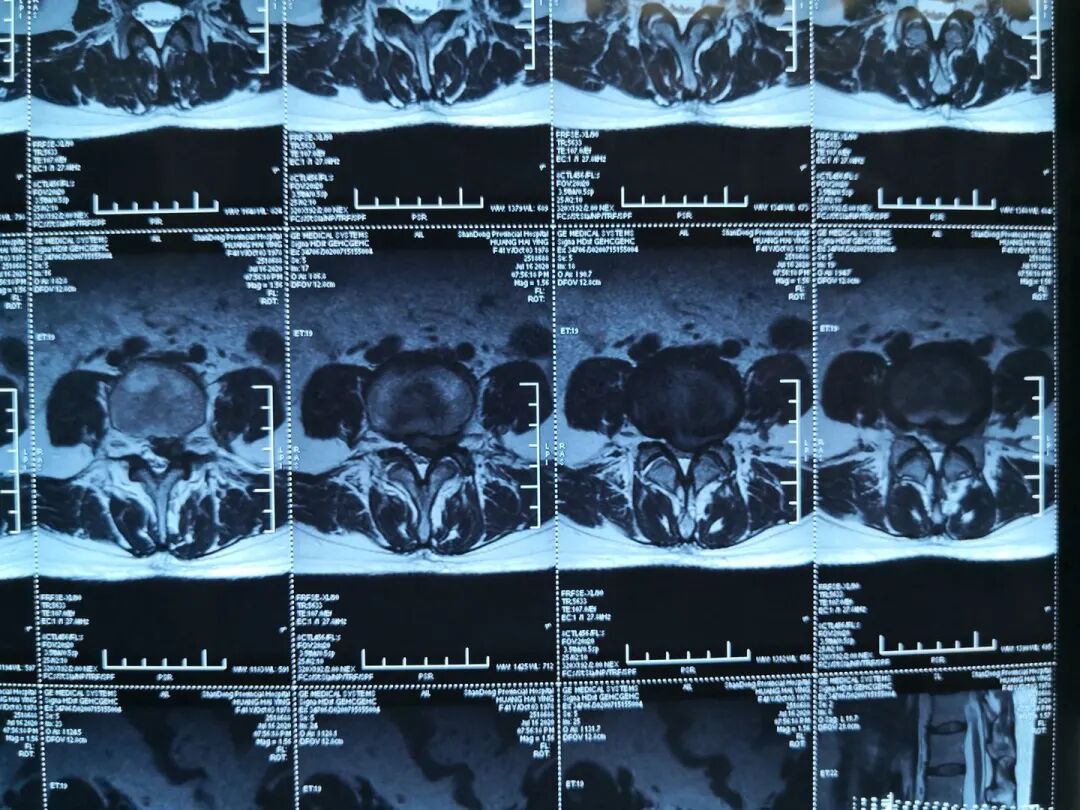

图6:术后磁共振

2020年7月,山东省立医院蒋振松教授顺利开展一例UBE镜下腰4/5椎管减压手术,本次手术全程采用了UBE专用综合器械包和专用等离子射频手术系统及专用耗材,手术独立完成并达到满意效果。

UBE技术是一项新兴的微创脊柱内镜技术,通过建立两个通道(一个视野通道,一个操作通道)进行手术操作,在UBE内镜辅助下可完成中央椎管、双侧神经根及侧隐窝狭窄的减压,并可在镜下进行椎间植骨融合的一项技术。双通道脊柱内镜手术系统完全弥补单通道椎间孔镜工作效率低、视野范围小、适应症少的缺点;以及大通道技术失血多,创伤面大、视野模糊的的不足之处。